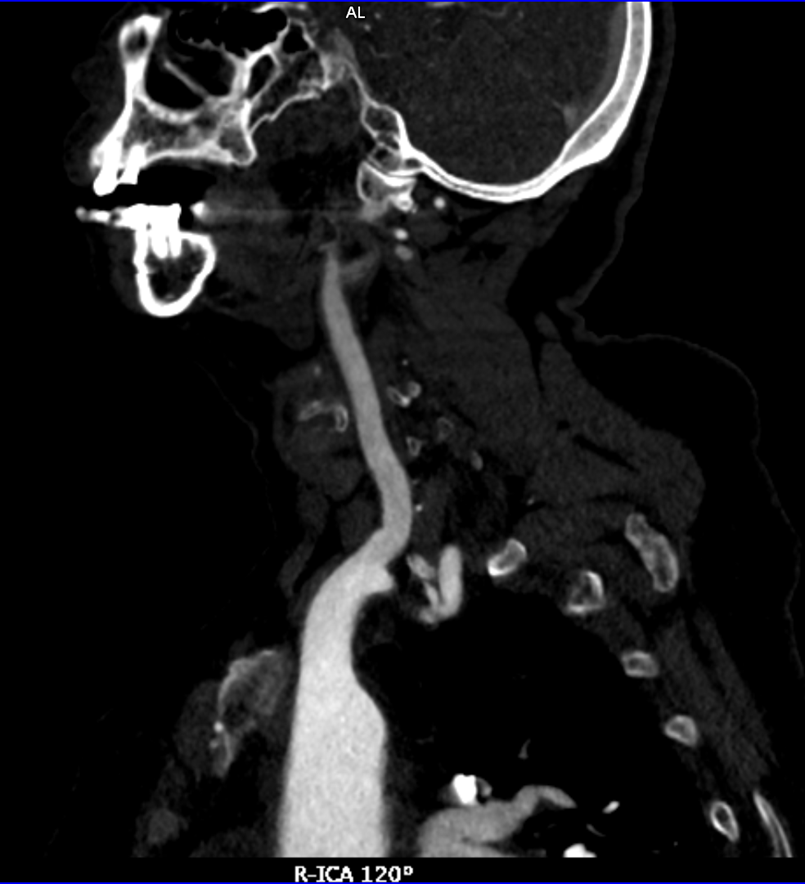

CTA

image.png  image.png

术前诊断:右侧颈内动脉闭塞;高血压病3级 极高危;持续性心房颤动;2型糖尿病;心脏瓣膜置换术后;肥厚型心肌病;肾功能不全;心功能不全。